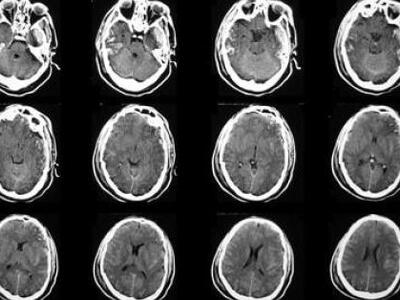

Στη συγκεκριμένη νευρολογική νόσο, το ίδιο το ανοσοποιητικό σύστημα επιτίθεται στην προστατευτική μεμβράνη της μυελίνης, η οποία περιβάλλει και μονώνει τα νεύρα του εγκεφάλου, του νωτιαίου μυελού και των ματιών.

Όταν η μυελίνη καταστρέφεται, τα ηλεκτρικά σήματα δεν είναι δυνατό να μεταδοθούν σωστά μέσων των νεύρων, με μια πληθώρα συνεπειών (μούδιασμα, παράλυση, τύφλωση κ.α.).